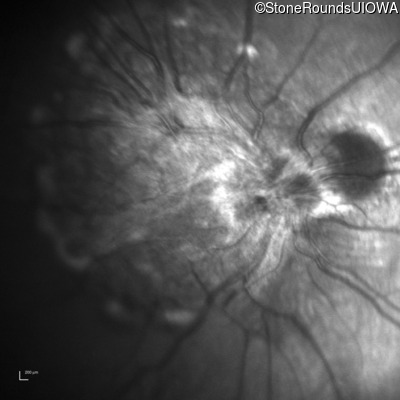

This 9 year old male was noted to have some crossing of his eyes at 2 months of age and the eye exam which followed identified a retinal lesion in the right eye. When he was six years old an epiretinal membrane was noted in his left eye. Two years later it was decided that it was a thin hamartoma in that eye as well. He underwent neuroimaging at age 7 which identified bilateral acoustic neuromas.

| Age at visit: 8 years |

| Age at visit: 10 years |

| Age at visit: 11 years |

| Age at visit: 14 years |